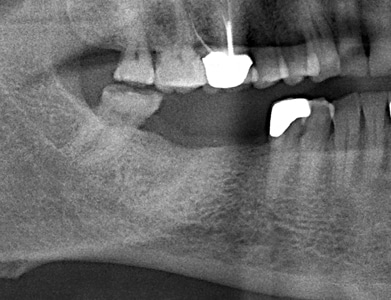

Crestal Sinus Elevation For Implant Placement

Introduction Challenges to implant placement in the posterior maxilla may be related to the maxillary sinus. The sinus may pneumatize (enlarge) related to sinus issues, patient age, how long the site has been edentulous or related to periodontal bone loss associated with the tooth that will or has been extracted.1> Hence, crestal bone height may … Read more